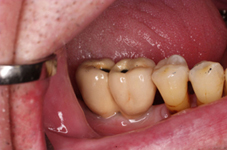

V případě chybění většího počtu zubů v postranních úsecích čelistí je možné ošetření pomocí implantátů, které nahradí ošetření pomocí snímacích náhrad kotvených na zbývajících zubech nebo patře.

Podmínkou je opět dostatečné množství kosti.

Protetické řešení může být pomocí můstku, který je kotvený na implantátech nebo pomocí jednotlivých korunek na implantátech.

V zásadě je možné do těchto můstků zařadit i přirozené zuby, zejména pokud je potřeba tyto zuby ošetřit proteticky – korunkami. Korunky nebo můstky mohou být na implantáty nacementovány nebo přišroubovány.

Zdravé zuby zůstanou zachovány a přitom náhrady jsou pevné, jako na vlastních zubech